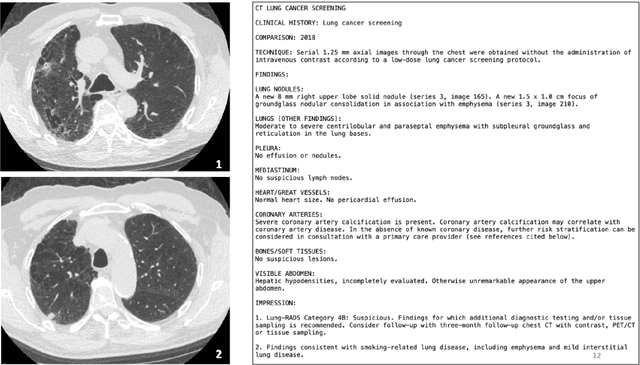

Abstract:Patients managing a complex illness such as cancer face a complex information challenge where they not only must learn about their illness but also how to manage it. Close interaction with healthcare experts (radiologists, oncologists) can improve patient learning and thereby, their disease outcome. However, this approach is resource intensive and takes expert time away from other critical tasks. Given the recent advancements in Generative AI models aimed at improving the healthcare system, our work investigates whether and how generative visual question answering systems can responsibly support patient information needs in the context of radiology imaging data. We conducted a formative need-finding study in which participants discussed chest computed tomography (CT) scans and associated radiology reports of a fictitious close relative with a cardiothoracic radiologist. Using thematic analysis of the conversation between participants and medical experts, we identified commonly occurring themes across interactions, including clarifying medical terminology, locating the problems mentioned in the report in the scanned image, understanding disease prognosis, discussing the next diagnostic steps, and comparing treatment options. Based on these themes, we evaluated two state-of-the-art generative visual language models against the radiologist's responses. Our results reveal variability in the quality of responses generated by the models across various themes. We highlight the importance of patient-facing generative AI systems to accommodate a diverse range of conversational themes, catering to the real-world informational needs of patients.